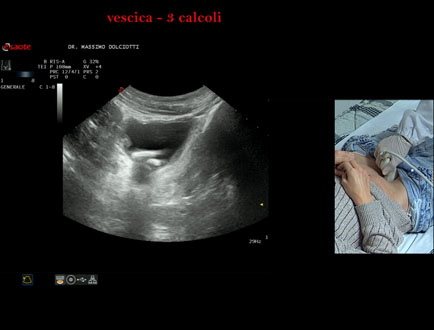

Sonda: Convex Multifrequenza 1-8 MHz

Età Paziente: F 45 anni

Motivazione dell'esame: da alcuni mesi, disuria ed infezioni urinarie recidivanti.

Commento all'esame: le immagini ed il video documentano 3 immagini iperecogene, con cono d'ombra posteriore, da ricondurre a litiasi multipla della vescica.

Conclusioni: 3 calcoli della vescica (3 bladder stones).